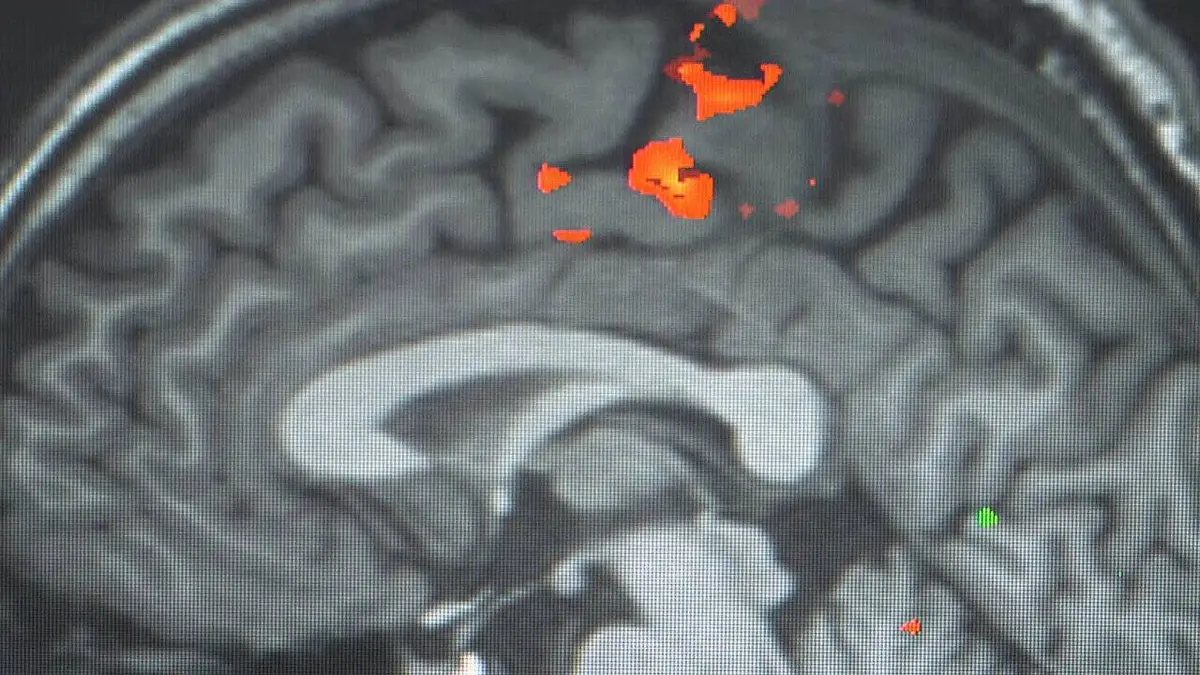

Je supprime la publicitéEnquête au coeur du Neurospin, le plus grand complexe mondial dédié à l'exploration du cerveau, une plateforme ultra-moderne qui repousse sans cesse les limites de l'imagerie cérébrale.

Vidéo Voir le cerveau penser